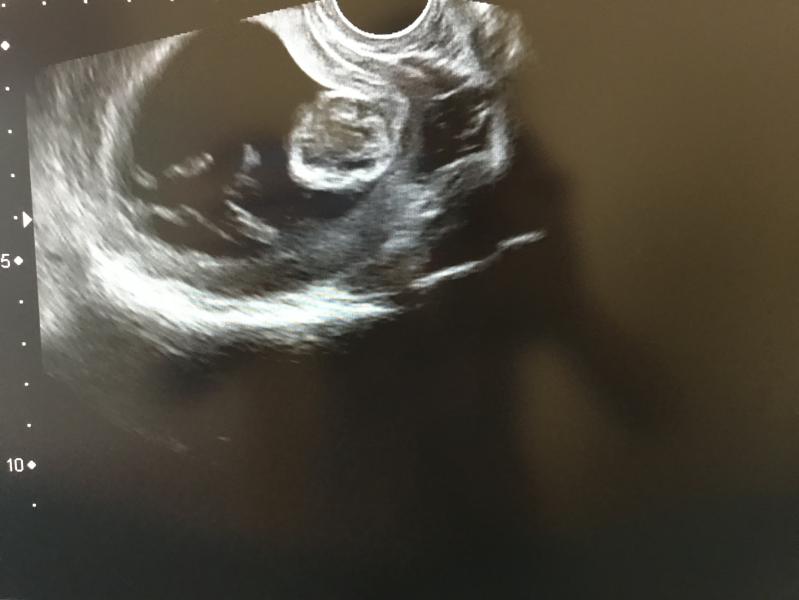

Ура! У нас есть первое фото.☺️Сегодня первый раз увидела своего малыша, эмоции не передаваемые 😌